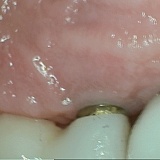

"FOLLOW UP" "BEWARE FOR DR. GAUKHMAN & VANESSA'S WORK:"

I filed a complaint against Dr. Gaukhman and his assistant with the B. B. B. And in his response to the B.B.B.he stated that I was happy with the shoddy work

That his assistant Vanessa performed- and he told the B. B. B. That I was still wearing it for the 11 months of treatment of the work that was a total failure for the two

Attempts with two different labs that Vanessa used, Dr. Gaukhman stated that I was still wearing the prosthesis- which is a TOTAL LIE, please see the copy of the letter that I am also providing for this review

From Dr. Larry Dunford stating that the prosthesis is in fact- in Dr. Dunford's possession, and has been since it was removed as not being fit to be used -as was stated in the letter from Dr. Dunford.

I am also submitting photos showing exactly what was wrong with the work that was performed by the assistant from Dr. Gakuhman's office.

Dr. Dunford was totally amazed to the fact, even though I emphasized to Dr. Gaukhman that the 6 dentist that I got opinions from, all stated that I needed to have only a prosthodontist dentist

Do the work on me, and certainly not an assistant as Dr. Gaukhman allowed- and not one single time did Dr. Gaukhman ever assist Vanessa's work -other than stating that he watches her on security

Cameras located in all of the exam rooms.

Dr. Misch said even though his wife is a prosthodontist she could not do my case as it was too complicated- and so Dr. Misch referred me to Dr. Dunford. As I needed a prosthodontist and not a

Non-professional un-trained person without any experience- nor any help did she ever get from Dr. Gaukhman to do the work that I desperately needed.

Dr. Dunford did 95% of my work alone on me- and in 10 visits that was performed before ever sending it off to the lab, and when the unit came back as a one piece Ziconia unit from the lab it was 100%

Perfect, not like the inferior and nonfunctional 4 separate piece units that Vanessa did- and that her work was in such an unprofessional manner and result, BUT instead I received a perfect functional

One piece unit -and aesthetically perfect from Dr. Dunford's work, We Sometimes Learn From Other Peoples mistakes-

"So Please Learn From My Mistake When I Didn't See The So Many Red Flags- And Got Taken For $27,000.00 From Dr. Gaukhman"

Please see the photo with no bite on the 6 front teeth, and the photo of excessive space on the abutments -and see the letter from Dr. Dunford that completed my work, as we sent a copy of his letter to

The B. B. B. Stating that he has the shoddy work that Vanessa performed- thus exposing Dr. Gaukhman in his serious lies when he responded to the B. B. B. And the nerve of him lying to make himself look good.